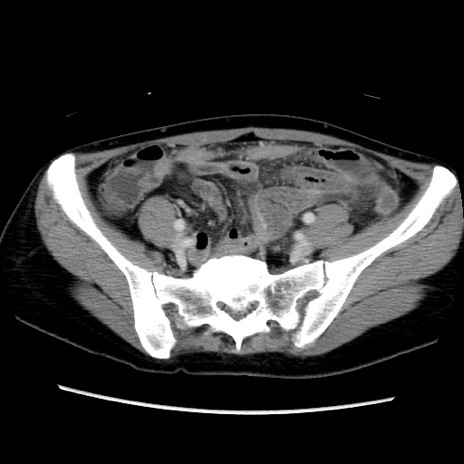

MRI(4日後)

【症例】40歳代女性

【主訴】上下腹部痛

【現病歴】2日目から下腹部痛あり。夜間は痛みで眠れなかった。昨日より上腹部痛と下痢が出現。臥位で痛みは軽快したため、休んでいた。本日になって臥位でも立位でも痛みが強くなってきたため救急要請。

【既往歴】子宮内膜症

【身体所見】部:平坦・軟、左上下腹部に圧痛あり、反跳痛あり。

【データ】WBC 21800、CRP 26.78